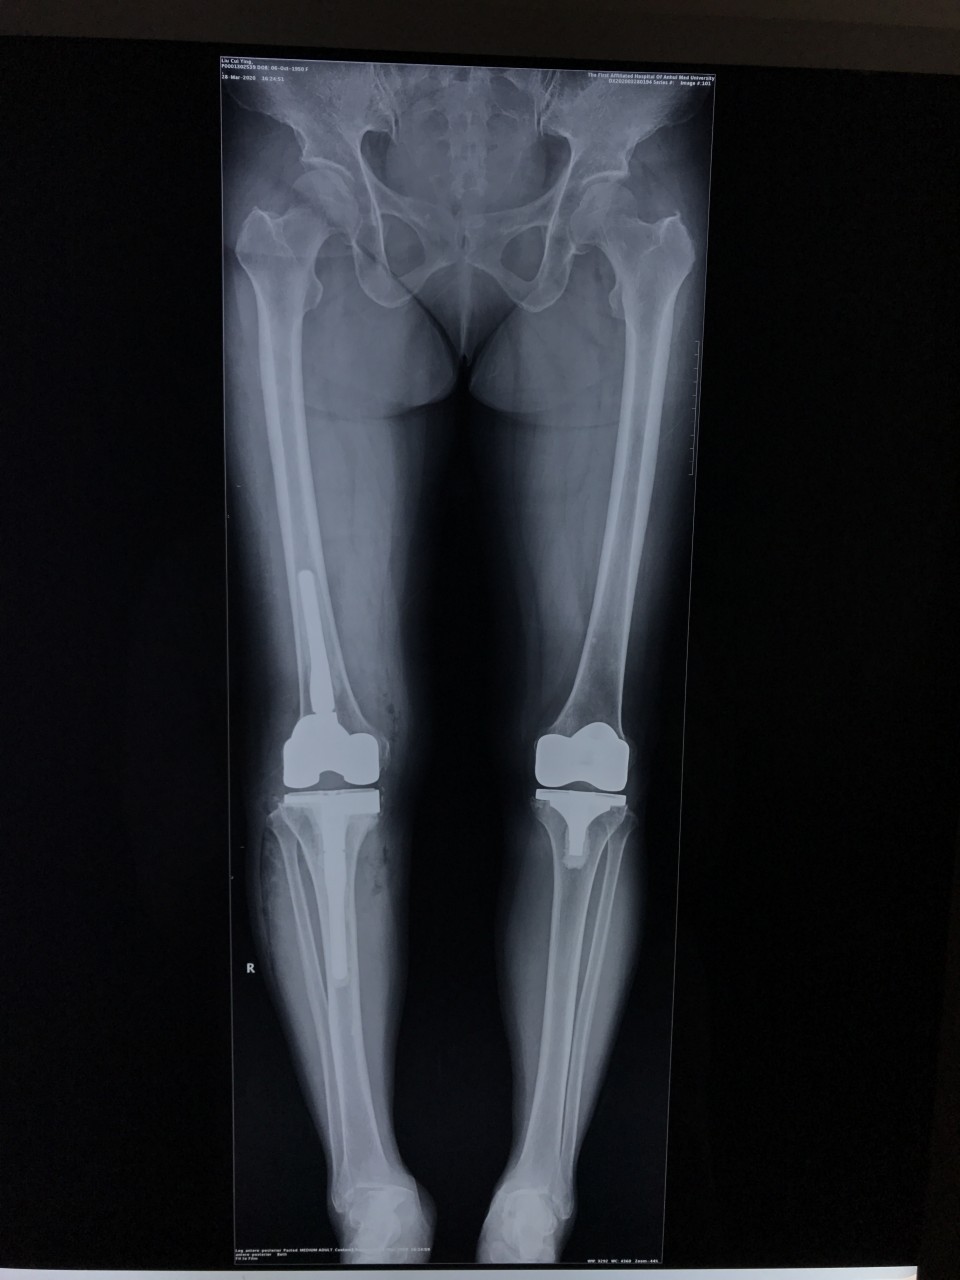

3月25日,一位69岁的女性患者因“右膝疼痛2年,加重伴活动受限1年”入院。术前摄片提示右侧膝关节假体松动。关节与显微修复外科胡孔足主任术前结合患者病史,体检及辅助检查,反复讨论,制定了精细的手术方案,术中假体安全取出,手术顺利。手术结束半小时,患者已经能够完全自主抬腿,屈曲。患者术后第二天下地正常行走。前后患者住院5天,快速康复出院。

人工关节翻修手术无论手术技术难度还是手术风险都要比初次人工关节置换大的多,而且感染风险也要比初次置换大,更有可能伴有大的骨缺损,手术方案需要精心制定。“快速康复外科”(ERAS)融合了麻醉、护理、康复、外科、以及营养等多学科理念。快速康复外科指采用证实有效的围手术期多模式优化管理措施,降低外科应激反应,降低术后疼痛,加速康复进程。ERAS应用于膝关节翻修患者具有明显优势,包括住院时间缩短、术后疼痛减轻、膝关节功能恢复优、术后失血量少、软组织损伤小、减少院内感染、住院费用少等,能够明显提高患者疗效及满意度。